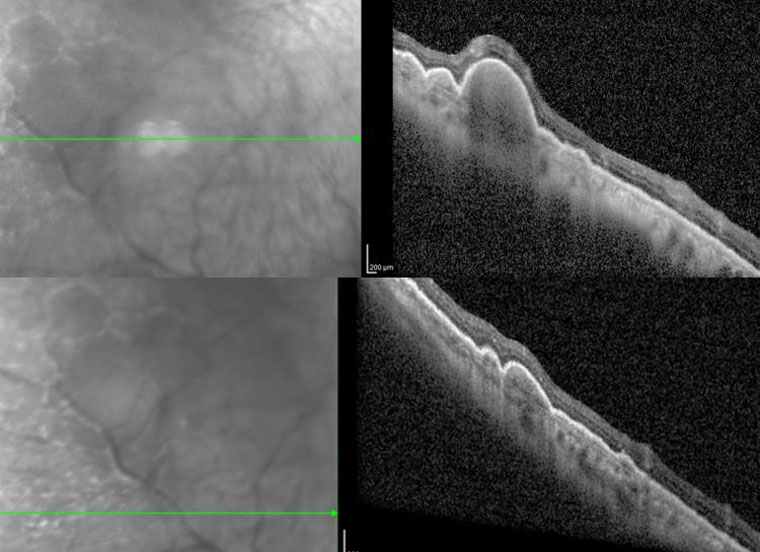

右眼OCT(光学相干断层扫描)

郝玉华主任及其团队仔细翻阅既往病例资料,完善相关眼科检查,根据双眼玻璃体内大量细胞、OCT提示视网膜外层结节样病变和眼底隐约可见黄白色病灶的症状,高度怀疑双眼眼内淋巴瘤合并中枢神经系统受累,经与患者及家属详细交代病情,决定行右眼诊断性玻璃体切除手术以明确诊断。